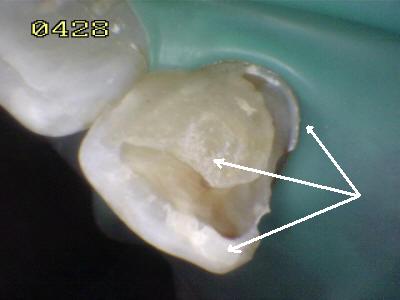

Eliminada la

caries, micro-arenado con óxido de aluminio y grabado total con

acido ortofosforico (Flechas blancas)